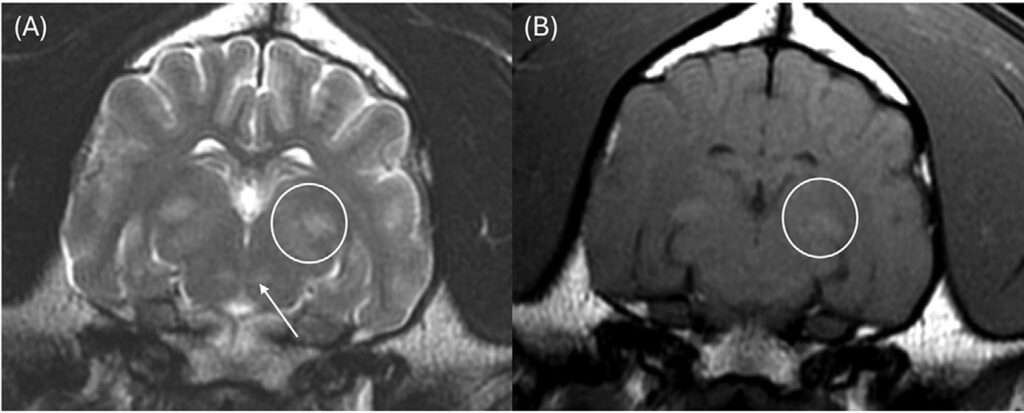

颈椎MRI图像大多未见异常,仅显示颈椎间盘纤维环的轻度非压迫性突出。脑部成像显示双侧对称、边界不清的T2和T2-FLAIR高信号,影响丘脑(图1A)、内侧和外侧膝状体(图2A)、导水管周围灰质和红核(图2A)。在双侧豆状核(图3A)、丘脑(图1B)和膝状核(图2B)内可见T1高信号。这些病变未显示对比增强。未在任何可见的骨或软组织结构中发现异常。

图1. 丘脑核(白色箭头)中可见双侧对称、边界不清的T2(A)和T1(B)高信号。

图2.(A)内侧和外侧膝状体区域(白色圆圈)及红核区域(白色箭头)可见双侧对称、边界不清的T2高信号;(B)内侧和外侧膝状体区域(白色圆圈)可见双侧对称、边界不清的T1高信号。